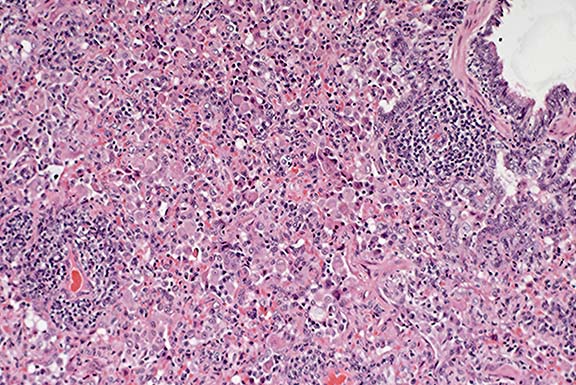

Case 9-2a. Neoplastic mast cells expand the sinusoids between necrotic hepatocytes (right). 40X

AFIP Diagnoses: 1. Liver: Mast cell tumor, malignant, Domestic Shorthair cat, feline. 2. Liver: Necrosis, coagulative, centrilobular, diffuse.

Conference Note: Although this feline lesion is often called mastocytosis, the diagnosis of malignant mast cell tumor was preferred because the term mastocytosis does not clearly indicate that the condition is neoplastic.

In cats with this form of mast cell neoplasia, splenomegaly due to massive infiltration of mast cells is consistently found. Other organs often involved include liver, lymph nodes, and bone marrow. Approximately 50% of affected cats have mastocytemia.